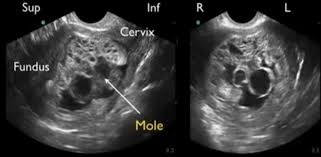

Infografis medis yang menunjukkan perbandingan struktur ginjal sehat dengan ginjal yang mengalami pengerutan (atrofi) akibat hipertensi kronis, serta daftar makanan rendah natrium bagi pasien.